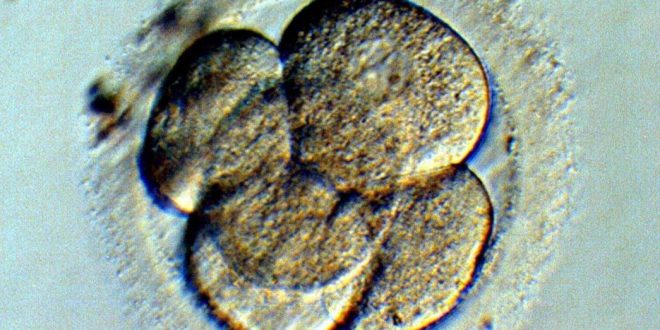

Antonio Lazcano Araujo, biólogo de la Universidad Nacional Autónoma de México, señaló que un embrión es un conjunto de células y no una persona.

El biólogo Antonio Lazcano Araujo, profesor e investigador emérito en la Facultad de Ciencias de la UNAM, explicó que “un embrión no es una persona” y afirmó que la vida no comienza en el momento de la fertilización, sino antes.

Una cosa es estar vivo y otra es ser una persona: un embrión no es una persona, es un conjunto de células”.

Para Lazcano Araujo, se puede hablar de vida desde la existencia de un espermatozoide y un óvulo pues “están vivos como un cigoto”, sin embargo, tanto la actividad nerviosa como la diferenciación celular, que da paso al sistema nervioso central en un embrión, inicia hasta la semana doce de gestación.

Antes no se puede decir que se trate de una persona o individuo en potencia, sino de una masa de células vivas que no son una persona, no tienen derechos sociales.